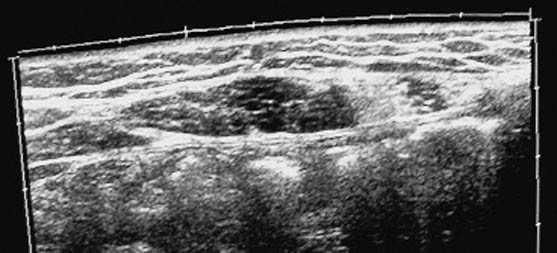

Aporta diverses exploracions complementàries: una ecografia abdominal, una ecografia ginecològica, una ecografia musculoesquelètica, un TAC abdominal, una gammagrafia òssia, una RMN i una anàlisi sanguínia. En el TAC abdominal es veu una imatge patològica al múscul recte de l'abdomen esquerre, compatible amb una cicatriu muscular (fig. 1). En l'ecografia ginecològica s'observa un quist fol·licular a l'ovari dret, al qual el ginecòleg no donà importància. En l'ecografia musculotendinosa es veuen dues cicatrius fibroses al múscul recte de l'abdomen esquerre a nivell diferent (fig. 2).

Figura 1